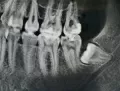

Вчера была у стоматолога. Предположение ― пульпит 8-ки, нужно удаление. Это первый коренной зуб, который предстоит удалить. Большой страх перед этой процедурой. Читала много, боюсь, чтобы не повредили лишнего. Корни 8-ки загнуты. Боюсь, чтоб они не лежали в нервном канале, и при удалении не было проблем.

Хочу сразу успокоить ― корни у нижней восьмерки в канале лежат очень редко, за 25 лет я такого не видел и даже не слышал. А вот корни верхних зубов бывает располагаются в гайморовой пазухе, вот это действительно сложное удаление. Нижние же зубы мудрости сложны в удалении только, если они лежат под костью, полностью заросли, так называемые ретинированные зубы.

Но у Вас, если его смотрел доктор и предположил пульпит, очевидно, что коронковая часть зуба видна. Даже, если корни загнуты, для хирурга-стоматолога ― это ординарная ситуация. Удаление, возможно, будет считаться сложным, но это означает лишь то, что врачу придется приложить чуть больше усилий.